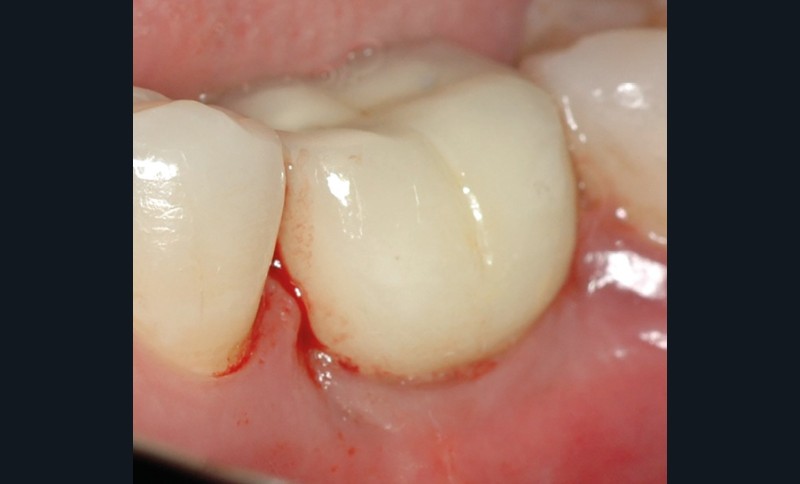

L’implant

- Avulsion de la 36 et régénération osseuse guidée (ROG) réalisée en 2017 suite à une fracture de la dent et une infection

- Un implant posé en 2018 après la fin du traitement orthodontique

- Couronne d’usage scellée, réalisée par son dentiste

- Péri-implantite diagnostiquée en 2021